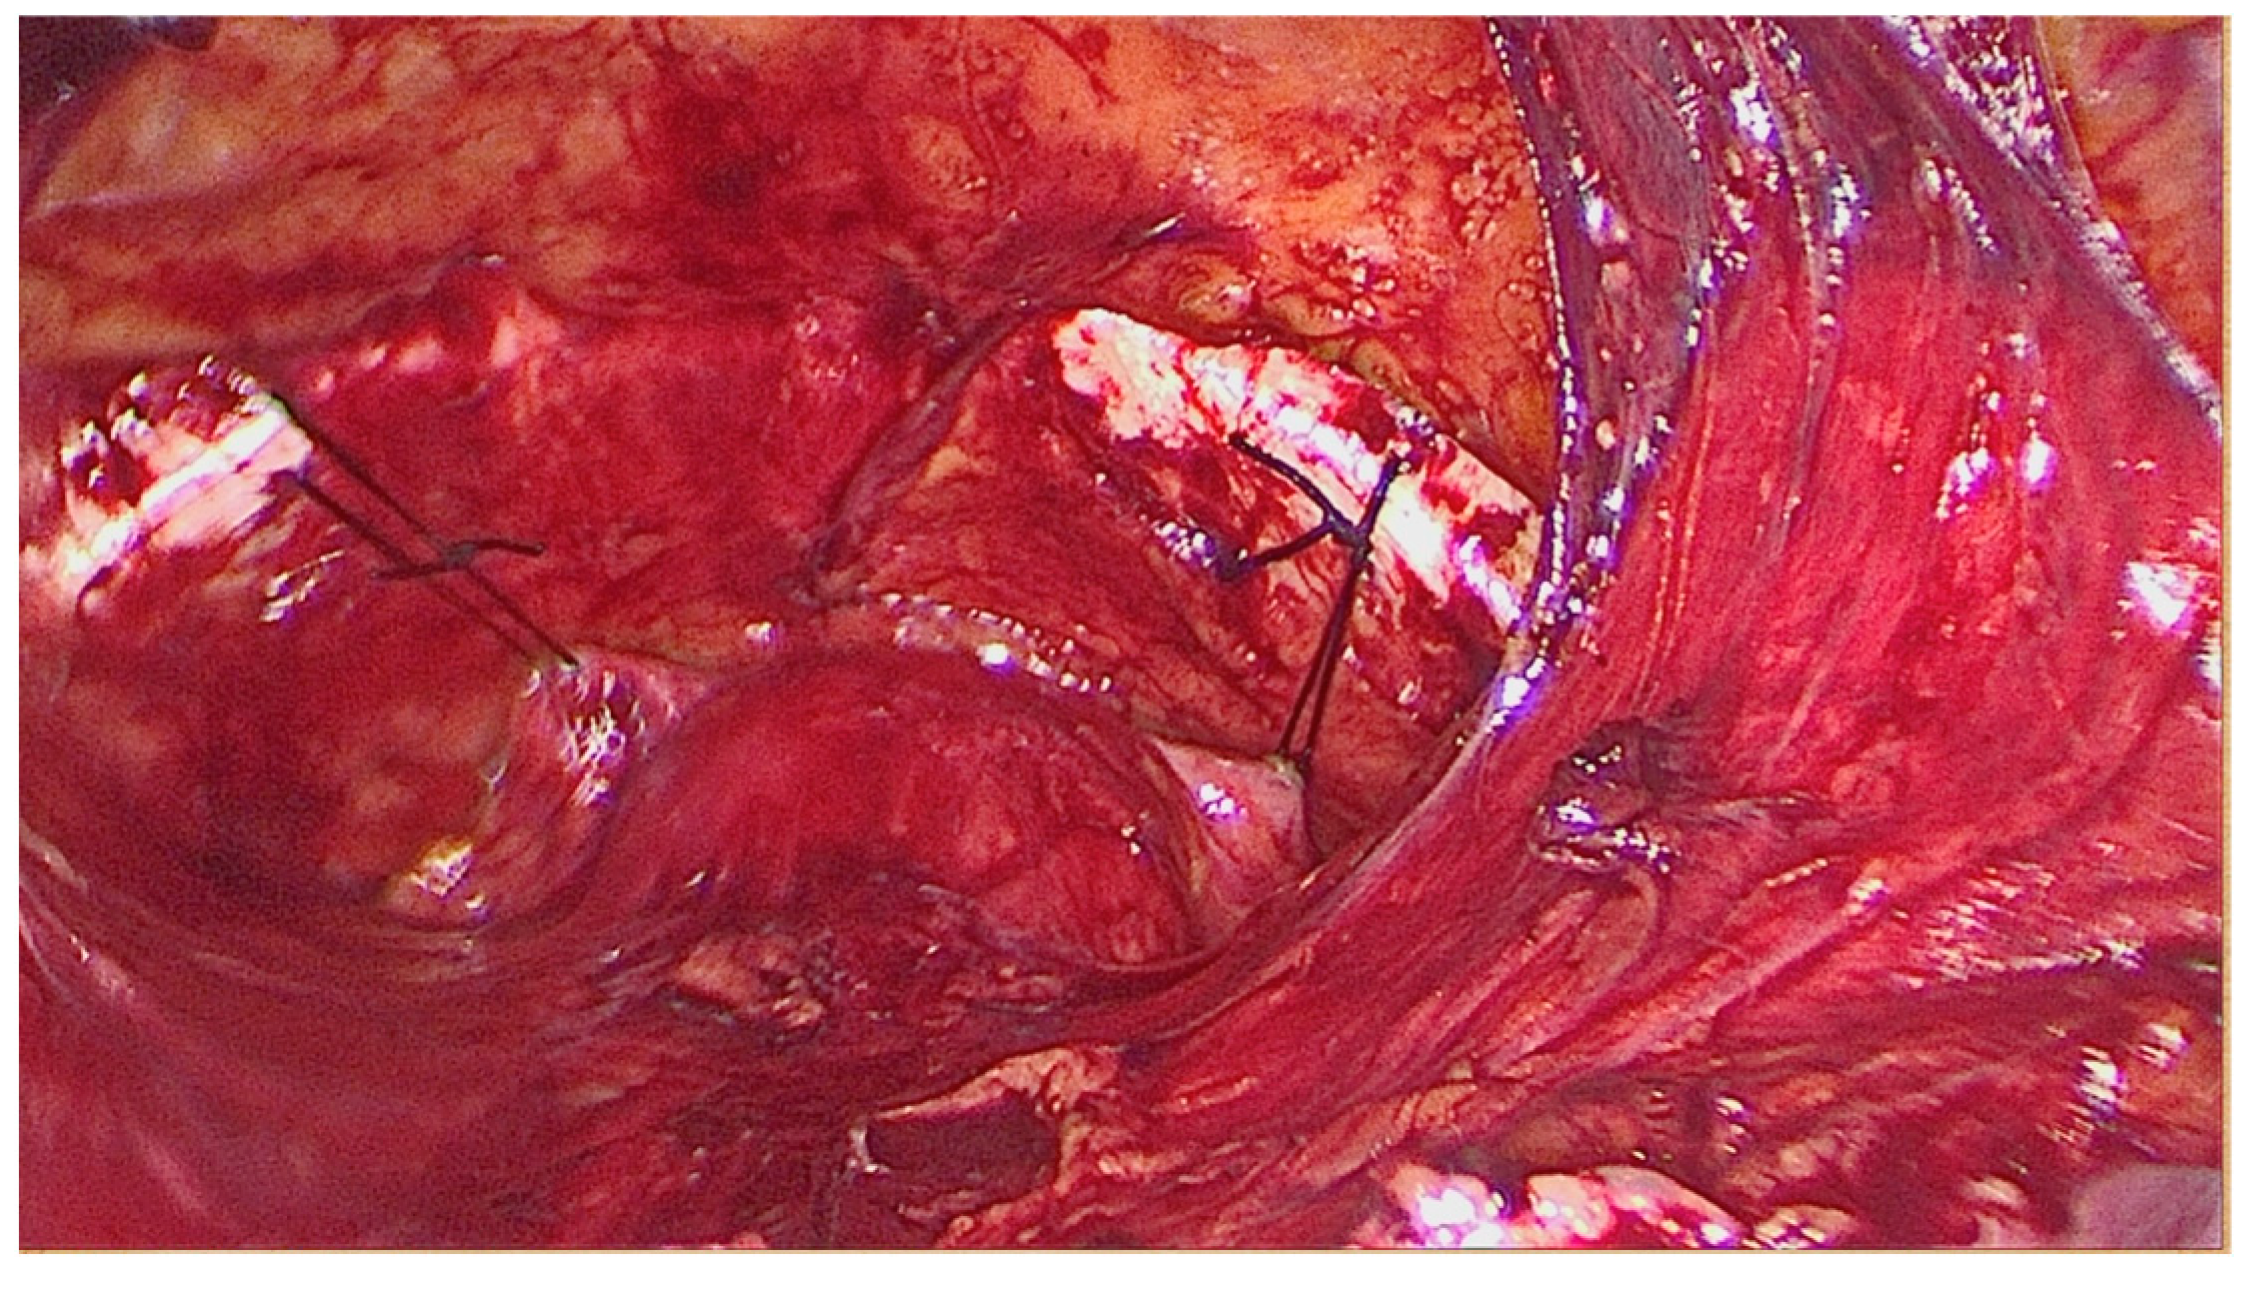

Figure 3.

The final aspect of modified laparoscopic Burch colposuspension technique with one thread on each Cooper ligament.

Direct entry is used to induce pneumoperitoneum. Prior to peritoneal incision, the bladder is filled with 250–300 mL saline solution in order to correctly expose the superior limit of the bladder dome to avoid blader injury at this level. Transperitoneal approach of Retzius space is achieved by performing an incision of approximately 5–6 cm of the parietal peritoneum between the two obliterated ombilico-vesical arteries superior to the bladder dome (upper vesical bladder limit). The bladder is drained after the peritoneum is incised and the avascular space of Retzius is developed by blunt dissection. The anatomical landmarks are represented by the pubic symphysis and the Coopers ligaments (Figure 2). The Foley catheter is also taken into account to identify the bladder neck. The vaginal walls are identified by blunt dissection with the aid of the assistant, who is lifting the vaginal wall through the vaginal route. Only one thread is placed on each side as follows: one bite through the medial part of each Cooper ligament and two bites on the vaginal wall caudally to the Foley catheter (in order to be placed in the mid urethral area) (Figure 3). The threads are knotted without creating extensive tension using intracorporeal knots. The parietal peritoneum is closed using a continuous suture. No drainage is needed. The Foley catheter is removed 24 h after surgery.